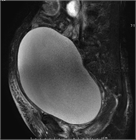

1. 尿閉とは膀胱内の尿を全く排出できないか、排出するのがきわめて困難な状態で、多量の残尿が常時ある状態である。